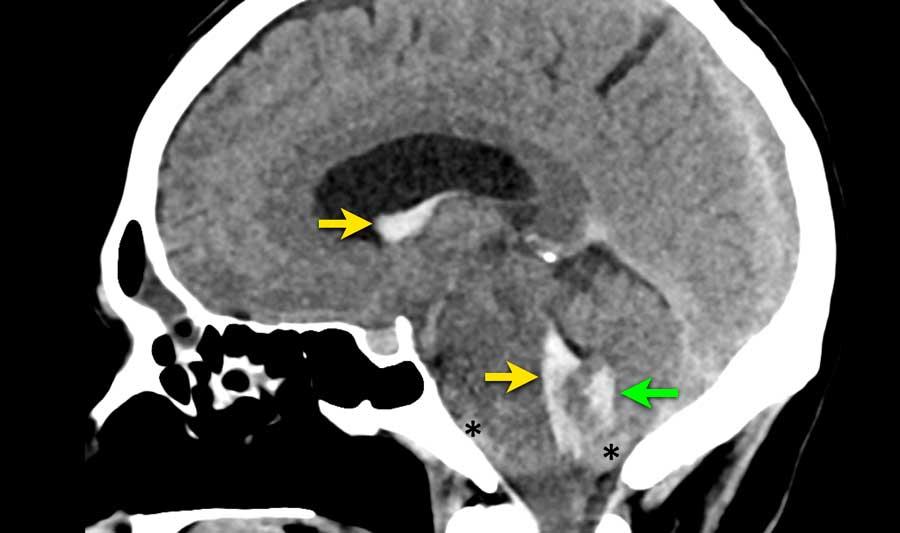

Bệnh nhân này nhập viện với triệu chứng đau đầu dữ dội khởi phát cấp tính.

Máu được phát hiện tại ba vị trí khác nhau:

- Trong não thất bên và não thất IV (mũi tên vàng)

- Trong nhu mô não tại vùng nhộng tiểu não (mũi tên xanh lá)

- Dưới nhện tại bể trước cầu não và lỗ chẩm (dấu hoa thị)

Tiếp tục với CTA…

CTA cho thấy động mạch tiểu não sau dưới (PICA) nổi bật (mũi tên vàng) với một túi phình hình túi 7 mm (vòng tròn) nằm tiếp giáp với nhộng tiểu não.

Có một tĩnh mạch giãn (mũi tên xanh dương) dẫn lưu trực tiếp vào xoang thẳng.

Giữa động mạch bất thường (PICA kèm túi phình) và tĩnh mạch bất thường, quan sát thấy một mạng lưới các cấu trúc mạch máu nhỏ (đầu mũi tên), nghi ngờ là nidus.